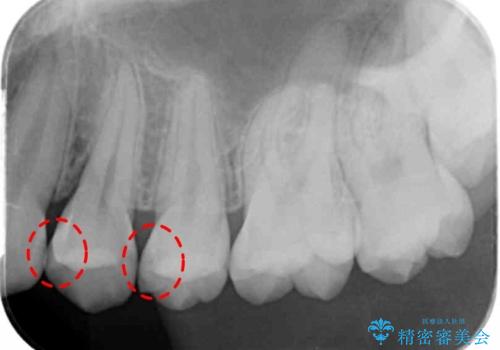

- 検査の結果、歯と歯の間に大きな虫歯が確認されました。

外から見て虫歯がないように見えても実は歯の中で大きく広がっていた、というケースは多く見受けられます。

症状なく進行していくことも少なくないため、定期的な検査はとても重要になってきます。

今回は残せる歯の厚みが十分確保できたため、インレーでの修復処置となりました。